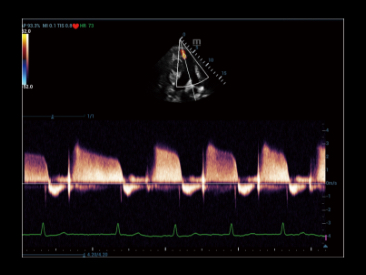

Dzi?ki technologii ZST+oraz Plane Waves, funkcja HiFR CEUS umo?liwia ultraszybk? wizualizacj? struktury naczyniowej i charakteru perfuzji w fazie t?tniczej.; mo?e s?u?y? jako narz?dzie uzupe?niaj?ce dla funkcji?UWN+

Przypadek kliniczny z wykorzystaniem technologii HiFR CEUS: Ogniskowy rozrost guzkowy w?troby

*?Nie zaleca si? stosowania HiFR CEUS w fazie p├│?nej lub na g??boko?ci 10 cm